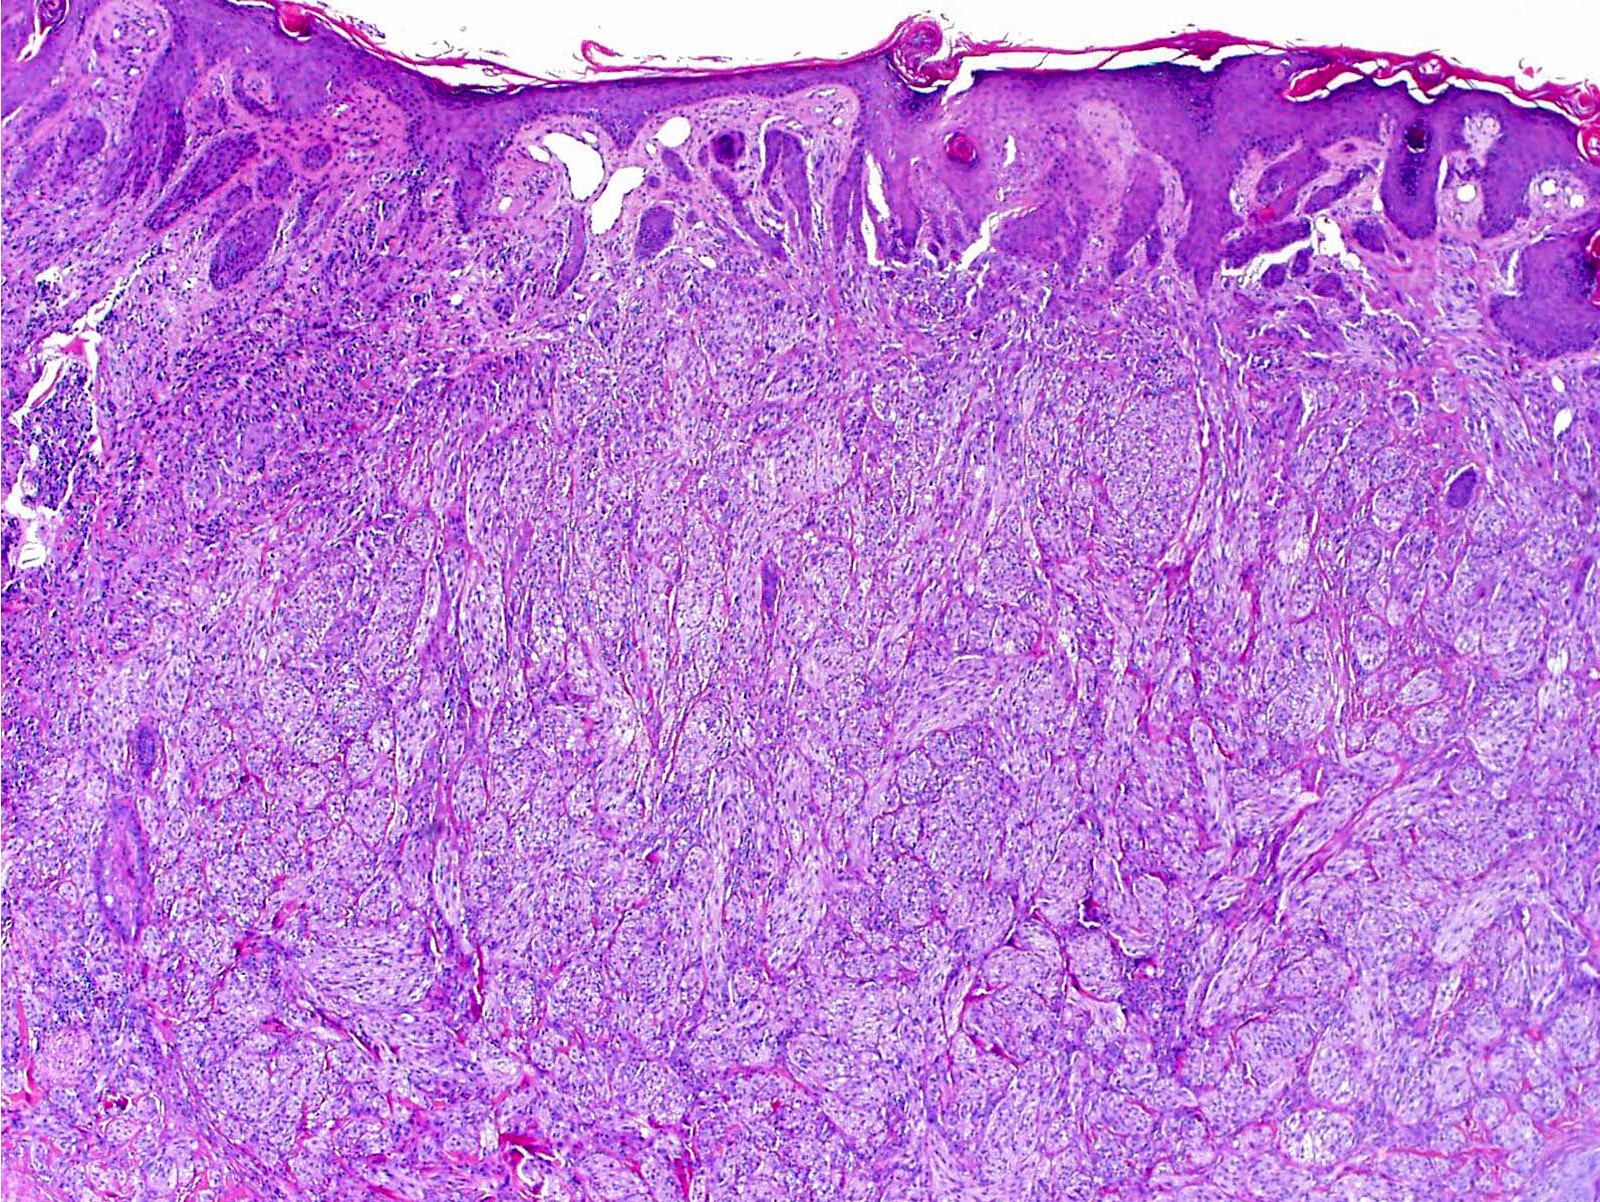

Microscopic (histologic) description

- Infiltrative or circumscribed architecture

- Can involve the subcutis

- Large polygonal cells with abundant eosinophilic granular cytoplasm and small, central nuclei

- Epidermis can show pseudocarcinomatous hyperplasia

- Lysosomal macroinclusions (pustulo-ovoid bodies of Milian) are usually present (J Cutan Pathol 2007;34:405)

- Can exhibit accentuation around arrector pili muscles or peripheral nerves (J Clin Pathol 2014;67:19)

Microscopic (histologic) images

Contributed by Jarish Cohen, M.D., Ph.D.